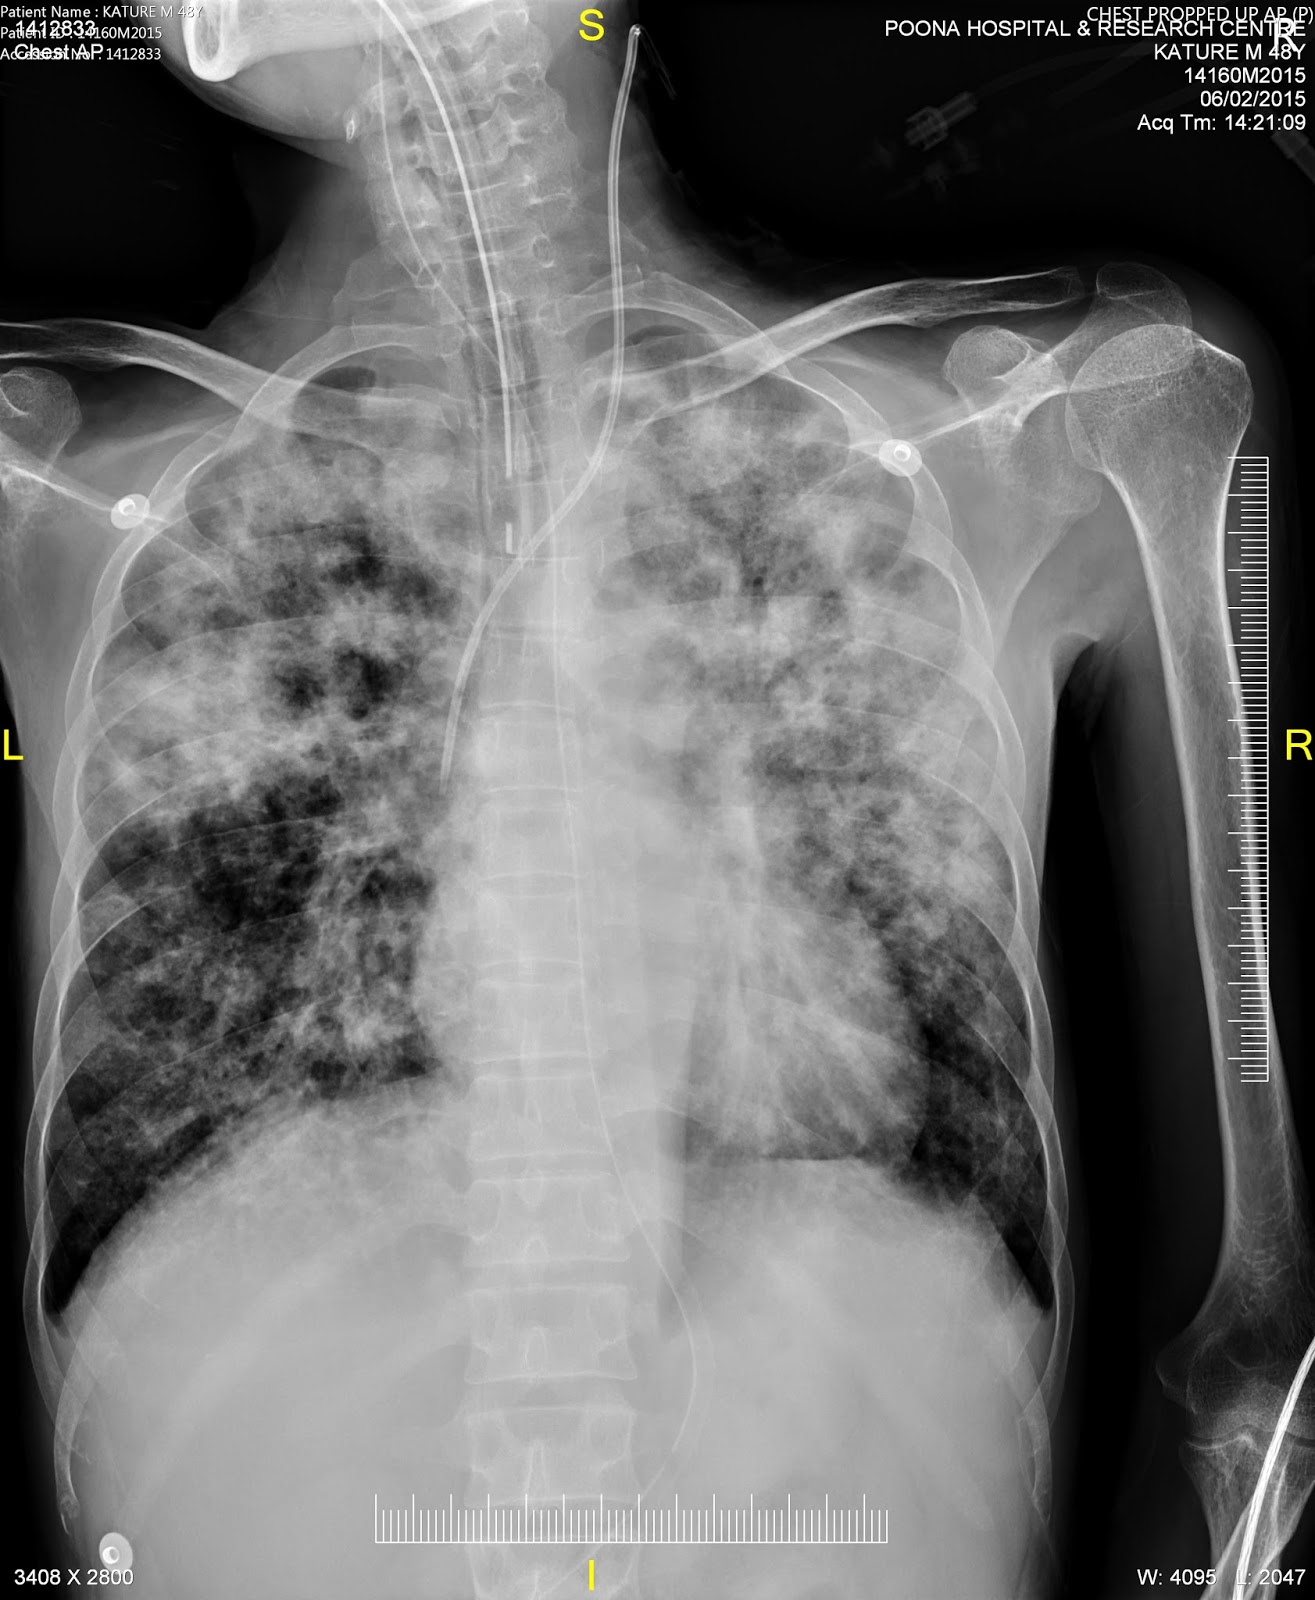

An elderly person accidentally ate a tablet along with its foil followed by severe chest pain.

There was a esopahegal tear with leak into the right pleural space. It was managed conservatively. After 1 month he developed right sided empyema. So the tear was sealed by a plugging device. Gastrograffin swallow done after the procedure did not reveal any leak.